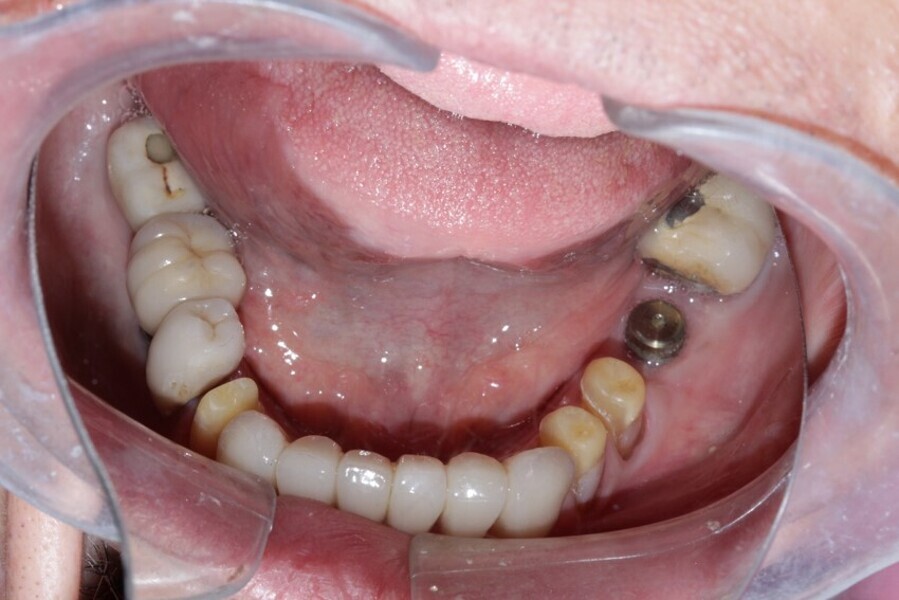

Figure 7 Mandibular occlusal view before treatment